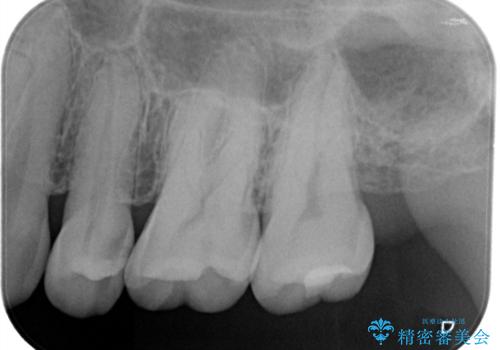

適合の良いセラミックインレー

- 定期検診して虫歯を認めたため、セラミックインレーにて修復治療を行なっております。

e-max プレスインレーにて修復治療を行っているため適合性及び審美性の高い治療を行うことができます